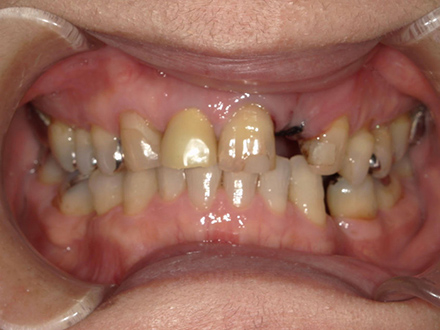

| 治療部位 | 上顎前歯部 |

|---|---|

| インプラント本数 | 4本 |

| 単価 | 40万円/本 |

| 合計費用 | 160万円 |